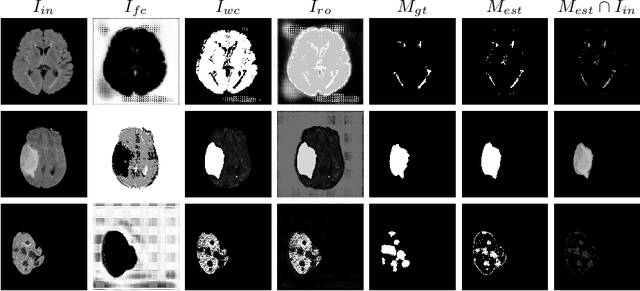

We introduce a neural network framework, utilizing adversarial learning to partition an image into two cuts, with one cut falling into a reference distribution provided by the user. This concept tackles the task of unsupervised anomaly segmentation, which has attracted increasing attention in recent years due to their broad applications in tasks with unlabelled data. This Adversarial-based Selective Cutting network (ASC-Net) bridges the two domains of cluster-based deep learning methods and adversarial-based anomaly/novelty detection algorithms. We evaluate this unsupervised learning model on BraTS brain tumor segmentation, LiTS liver lesion segmentation, and MS-SEG2015 segmentation tasks. Compared to existing methods like the AnoGAN family, our model demonstrates tremendous performance gains in unsupervised anomaly segmentation tasks. Although there is still room to further improve performance compared to supervised learning algorithms, the promising experimental results shed light on building an unsupervised learning algorithm using user-defined knowledge.